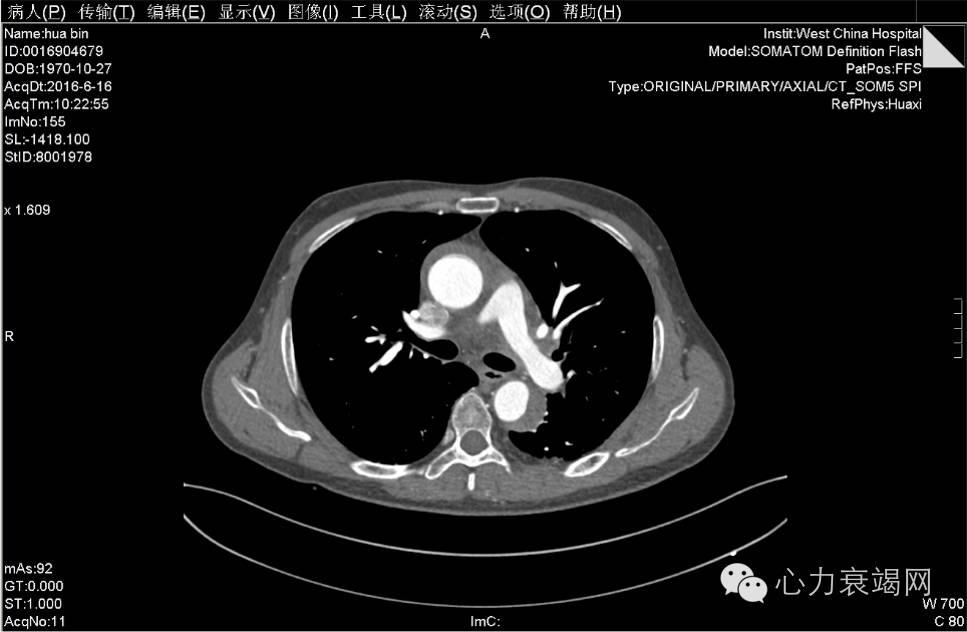

夹层动脉瘤CT

CTA示:主动脉壁内血肿,起自升主动脉根部,至降主动脉下段,并累及头臂干、左颈总动脉、左锁骨下动脉起始处,主动脉弓水平壁内血肿内见团片状低密度影,并见内膜小破口,增强见造影剂由破口进入壁内血肿,考虑局限性夹层?或其他,请结合临床。脾动脉稍迂曲。心脏稍增大,心包少许积液或心包增厚,主动脉壁少许钙化。双肺少许炎症,下叶为主。双侧胸腔少许积液或胸膜增厚。肝左外叶小囊肿。肝右后叶钙化灶。左肾囊肿。